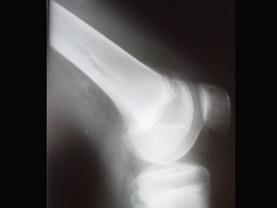

问题 病例,女,15岁,因感右股骨下段不适,不痛不胀,体查无特殊,请结合所提供的图像,选择最佳选项是 ( )

选项 A、良性骨肿瘤 B、骨结核 C、非骨化性骨纤维瘤 D、骨囊肿 E、纤维性骨皮质缺损

答案 E